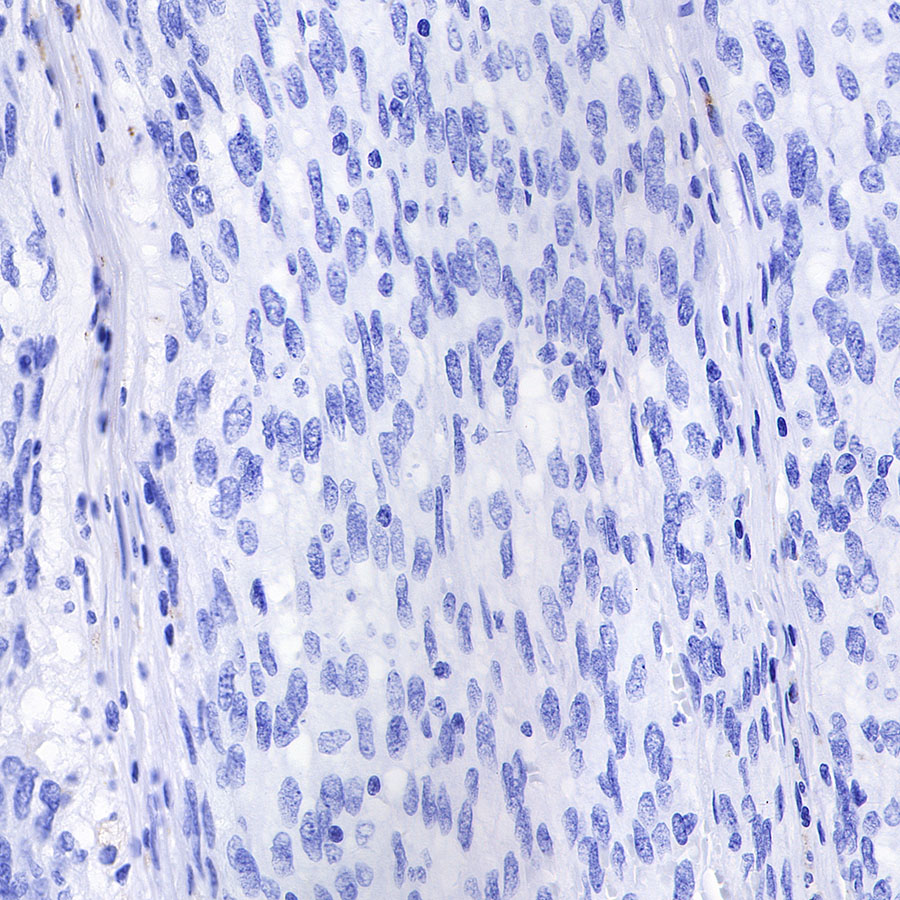

Negative control: IHC shows negative staining in paraffin-embedded human gastrointestinal stromal tumor. Anti-CD68 antibody was used at 1/1000 dilution, followed by a HRP Polymer for Mouse & Rabbit IgG (ready to use). Counterstained with hematoxylin. Heat mediated antigen retrieval with Tris/EDTA buffer pH9.0 was performed before commencing with IHC staining protocol.